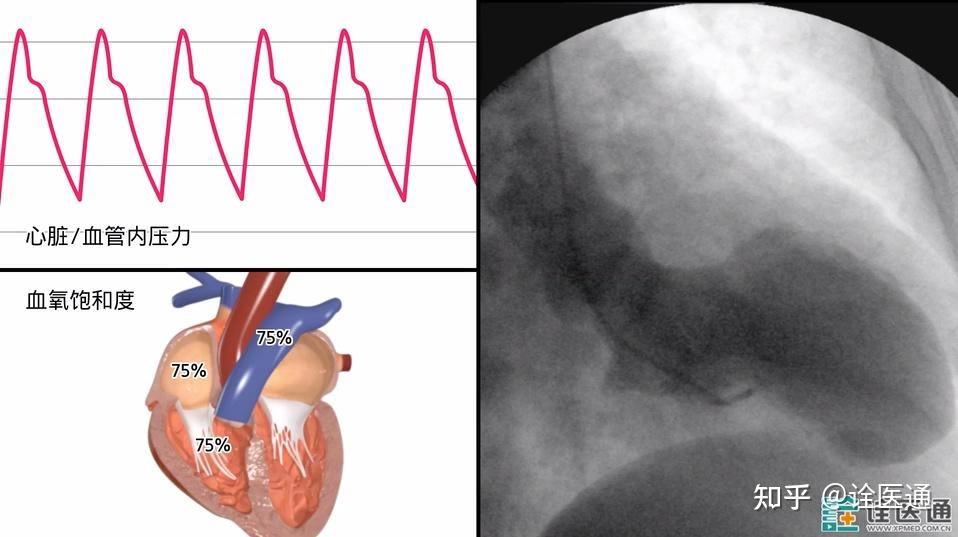

法洛四联症的心导管与造影检查

右心导管检查术02异常左心导管图形-限制性心肌病:通过侵入性血流动力